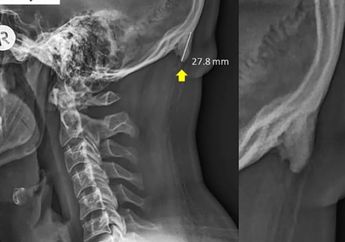

Gadget Ubah Kebiasaan Orang Jadi Sering Menunduk, Peneliti Temukan Fenomena Mengejutkan pada Tengkorak Manusia Generasi Muda!

6 Tahun yang lalu - Peneliti dapatkan penemuan yang mengejutkan pada tengkorak generasi muda yang diakibatkan oleh kebiasaan sering menunduk karena gadget.